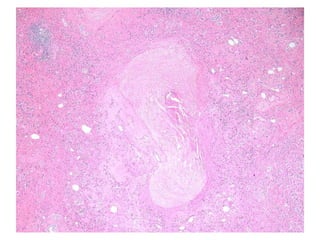

BS09-15303  Clinical history: 56 yo, female. elevated transaminase and anti-mitochondrial antibody.

BS09-15303  Dx: Primary biliary cirrhosis, Scheuer stage 1/4 (Diagnostic biopsy).